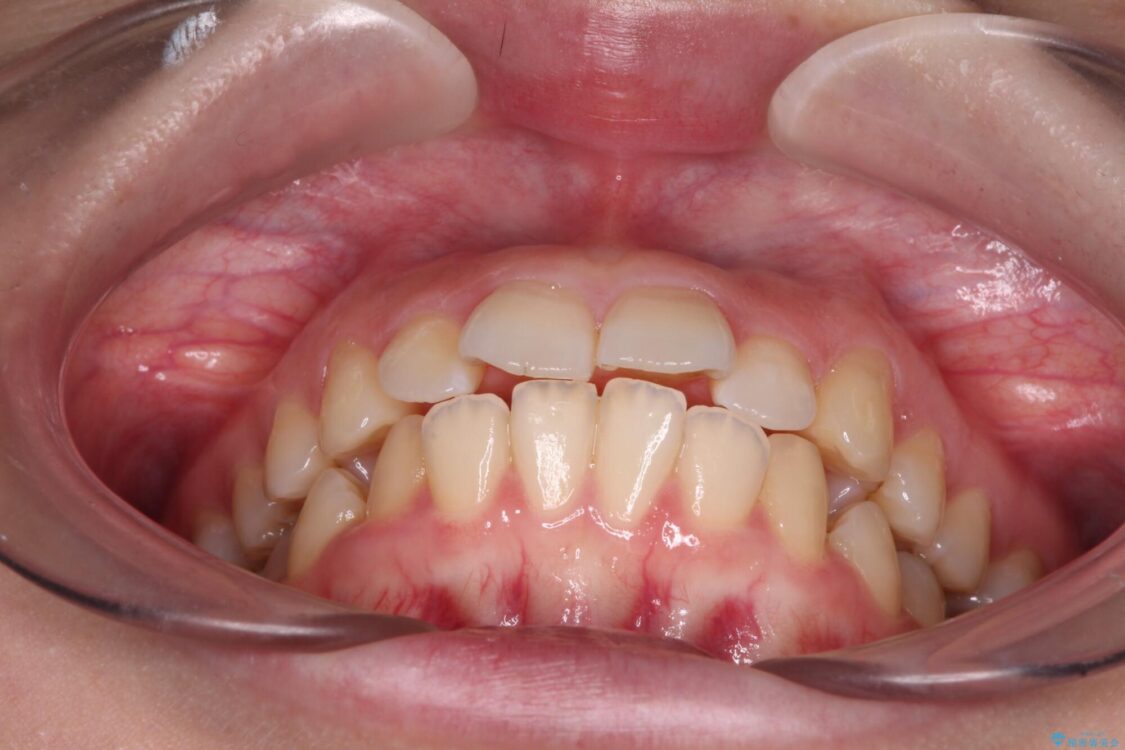

上下の前歯が突出しており、口が閉じにくいとのことで来院された患者様です。

上下前歯が著しく前突している状態であったので、上下左右の第1小臼歯4本を抜歯し、ワイヤー装置にて矯正治療を行うこととしました。

舌の突出癖により、前突になったと考えられたため、舌のトレーニングをしっかりと行うよう指導しました。